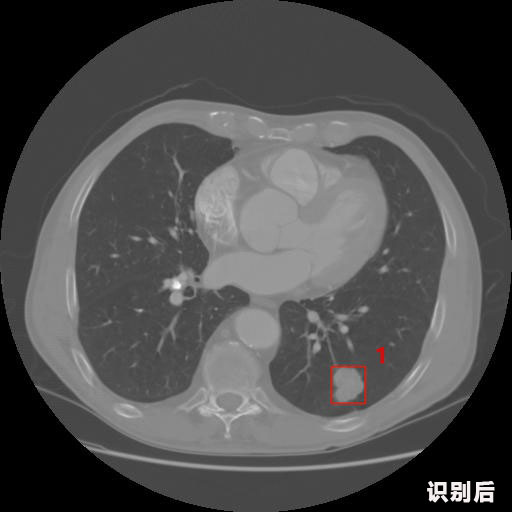

英特健康AI深度學習醫(yī)療圖像識別系統(tǒng)案例_胸部CT

1.發(fā)現(xiàn)肺結節(jié)的可能性為95.56%---位于框指數(shù)位置:[331.70554 366.13406 365.21707 403.96234]